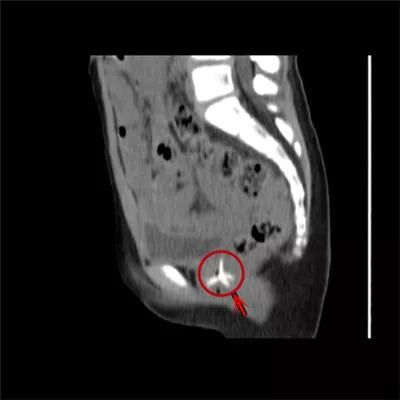

7岁·阴道异物

塑料玩具

家长发现内裤上分泌物增多,结果是阴道里一年前塞进了个塑料玩具。

文章图片